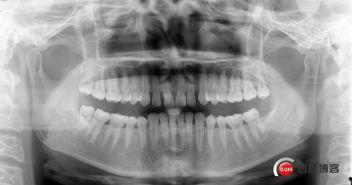

视频中,我们可以看到医生如何通过X光片确定多生牙的位置,然后进行局部麻醉。麻醉过后,医生使用专业的工具将多生牙从牙床中取出。整个过程大约需要30分钟左右。

1. 术前准备:医生首先通过X光片确定多生牙的位置,然后为患者进行局部麻醉。